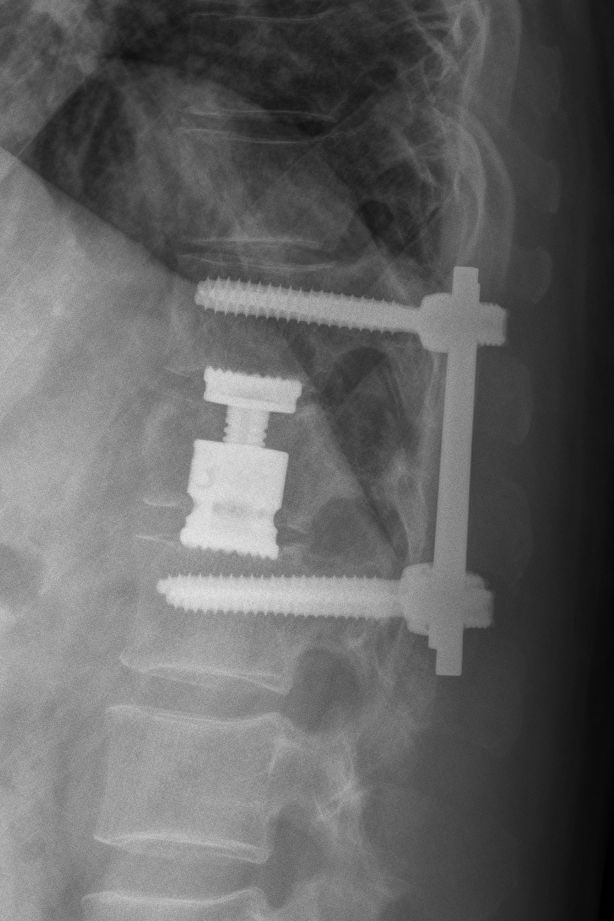

• Tříštivá zlomenina obratle T12 po kombinovaném ošetření vnitřním fixátorem v rozsahu T11-L1

Jednotlivé procedury se při operačním výkonu prolínají a fungují společně. Pro zajištění primární pooperační stability ze zadního přístupu používáme v krční i torakolumbální oblasti vnitřní fixátory. Jejich součástí jsou šrouby případně háky a spojovací tyče překlenující poraněný páteřní segment. Z předního přístupu jsou nejčastěji aplikovány kostní štěpy nebo klece přemostěné dlahou v krční oblasti, expandibilní klece a fixátory v torakolumbální oblasti. Všechny fixační prvky jsou vyrobeny ze slitiny titanu, která omezuje negativní stíny na vyšetření CT a jsou MR kompatibilní. Pro dosažení trvalé kostní stability používáme přemostění poraněného obratle nebo obratlů kostními štěpy z lopaty kosti kyčelní nebo syntetickou náhradu (trikalciumfosfát, hydroxiapatit).